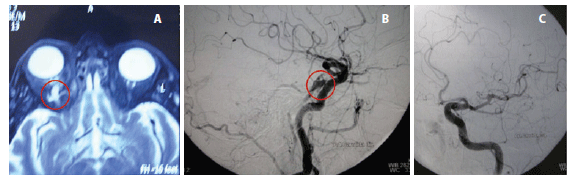

A ressonância magnética com contraste demonstrou proptose discreta à direita, veia oftálmica superior direita ectasiada e fístula carótido-cavernosa (Figura 2A). Mesmo com o uso de medicação tópica hipotensora (latanoprost 0,005% colírio 1x ao dia e brinzolamida 1% colírio 3x ao dia) a PIO sofreu uma elevação para 34 mmHg no olho direito. O neurologista recomendou a realização de uma arteriografia para embolização da fístula. Na arteriografia constatou-se a presença de uma fístula carótido-cavernosa indireta junto ao seio cavernoso direito, nutrida por ramos durais das artérias carótidas internas e da artéria carótida externa direita (Figura 2B). O exame da carótida esquerda revelou-se normal (Figura 2C). No mesmo ato foi realizado o tratamento endovascular, onde cateterizou-se seletivamente a fístula, e foram depositadas micromolas em seu interior associado a um balão destacável. Não houve intercorrências durante este procedimento.